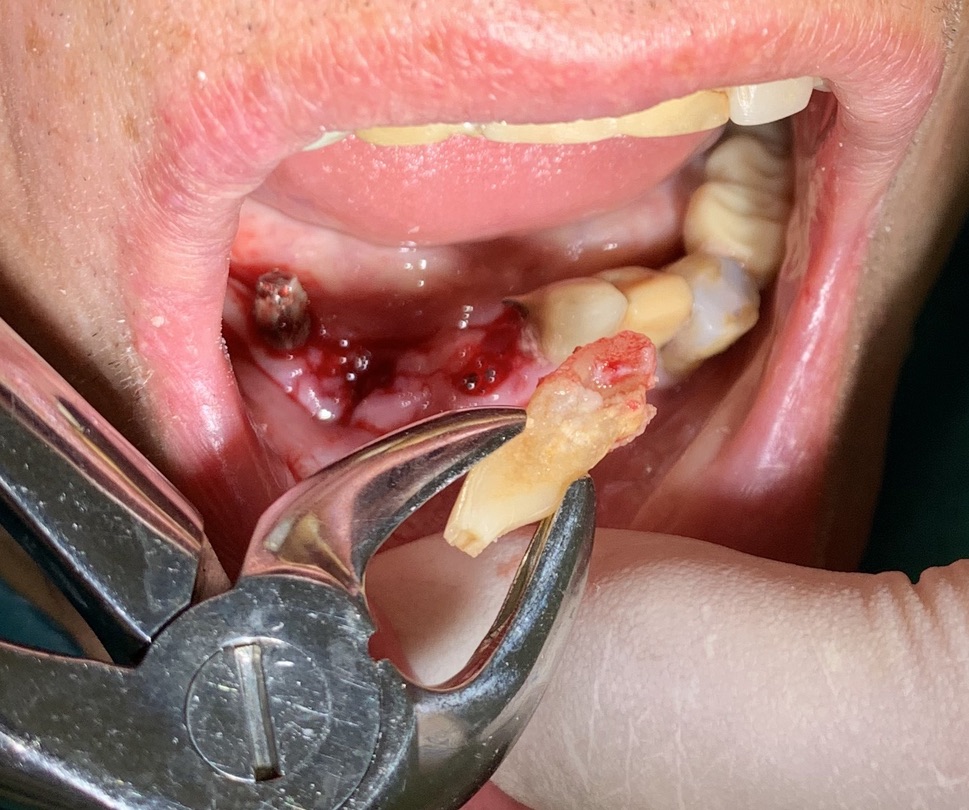

Situazione estrattiva: impianti postestrattivi immediati

Sequenza frese: solo lanceolata

Sequenza maschiatori: no maschiatori

Descrizione intervento:  Inizio intervento ore 9.00. Fine ore 11.45. NB intervento in anestesia generale richiesto dal paziente.

Complicanze    Nessuna                                                                                                   -